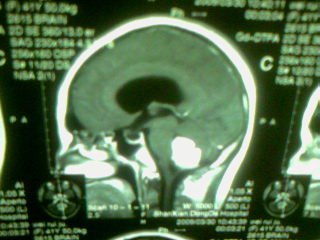

标题: MRI2125:女 45岁 头疼头晕3个月 [打印本页]

标题: MRI2125:女 45岁 头疼头晕3个月

手机照的,请各位谅解

1)考虑第四脑室脉络膜丛乳头状瘤,不排除室管膜瘤。2)阻塞性脑积水。

考虑 第四脑室室管膜瘤或脉络膜丛乳头状瘤伴梗阻性脑积水。

1)考虑第四脑室室管膜瘤,不排除脉络膜丛乳头状瘤。2)阻塞性脑积水。

第四脑室脉络丛乳头状瘤,典型!